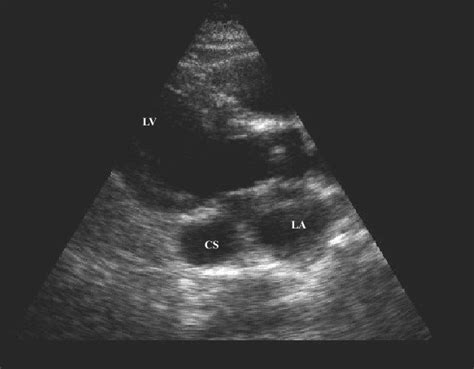

Longitudinal sections through two chambers. 132 avoid aorta and coronary sinus using simpson's rule how do you determine when to trace the diastolic volume? Right and left coronary cusps of the aortic valve. The cs could tolerate arterial pressure for a long period of time, and there was not a. The lv lateral wall, apex and septum are typically laid out.

Figure 1:Role of Echocardiography in Sinus Venosus Atrial ...

Figure 1:Role of Echocardiography in Sinus Venosus Atrial ... from openi.nlm.nih.gov

Apical 2 chamber, coronary sinus.